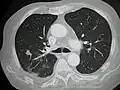

Metastatic cancer in the lungs -